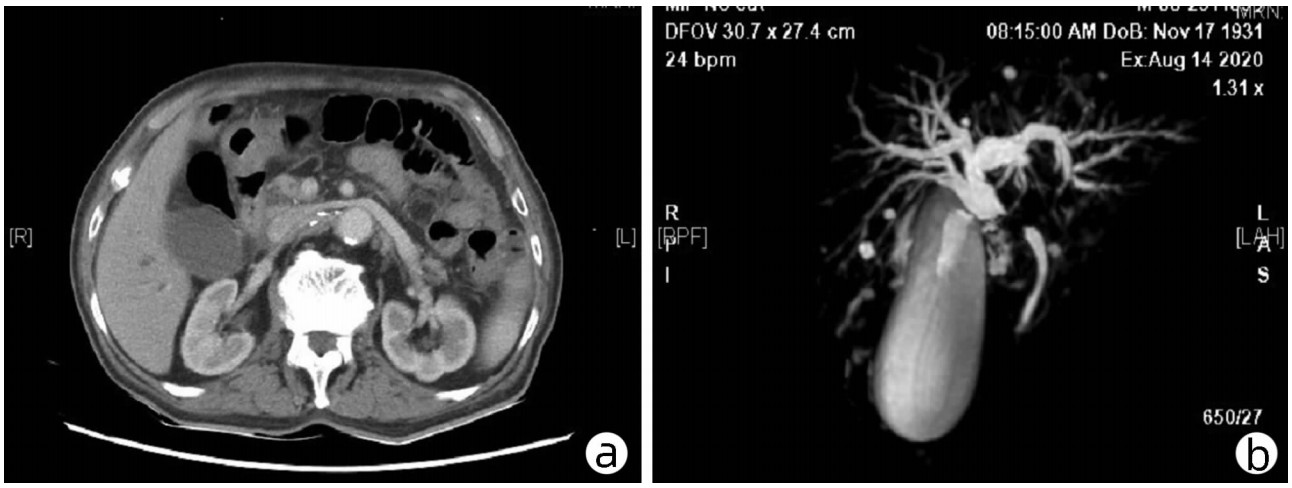

巨块型肝细胞癌转化治疗1例报告

李思柔, 周元龙, 刘珂良, 梁志波, 李靖华

2022, 38(7): 1612-1615. DOI: 10.3969/j.issn.1001-5256.2022.07.028

摘要(951) HTML (402) PDF (2763KB)(70)

摘要: